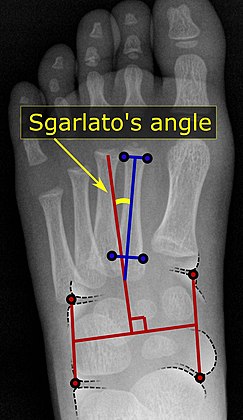

Pigeon toe can be diagnosed by physical examination alone.[10] This can classify the deformity into "flexible", when the foot can be straightened by hand, or otherwise "nonflexible".[10] Still, X-rays are often done in the case of nonflexible pigeon toe.[10] On X-ray, the severity of the condition can be measured with a "metatarsus adductus angle", which is the angle between the directions of the metatarsal bones, as compared to the lesser tarsus (the cuneiforms, the cuboid and the navicular bone).[11] Many variants of this measurement exist, but Sgarlato's angle has been found to at least have favorable correlation with other measurements.[12] Sgarlato's angle is defined as the angle between:[9][13]

• A line through the longitudinal axis of the second metatarsal bone.

• The longitudinal axis of the lesser tarsal bones. For this purpose, one line is drawn between the lateral limits of the fourth tarsometatarsal joint and the calcaneocuboid joint, and another line is drawn between the medial limits of the talonavicular joint and the 1st tarsometatarsal joint. The transverse axis is defined as going through the middle of those lines, and hence the longitudinal axis is perpendicular to this axis.

This angle is normally up to 15°, and an increased angle indicates pigeon toe.[9] Yet, it becomes more difficult to infer the locations of the joints in younger children due to incomplete ossification of the bones, especially when younger than 3–4 years.[citation needed]